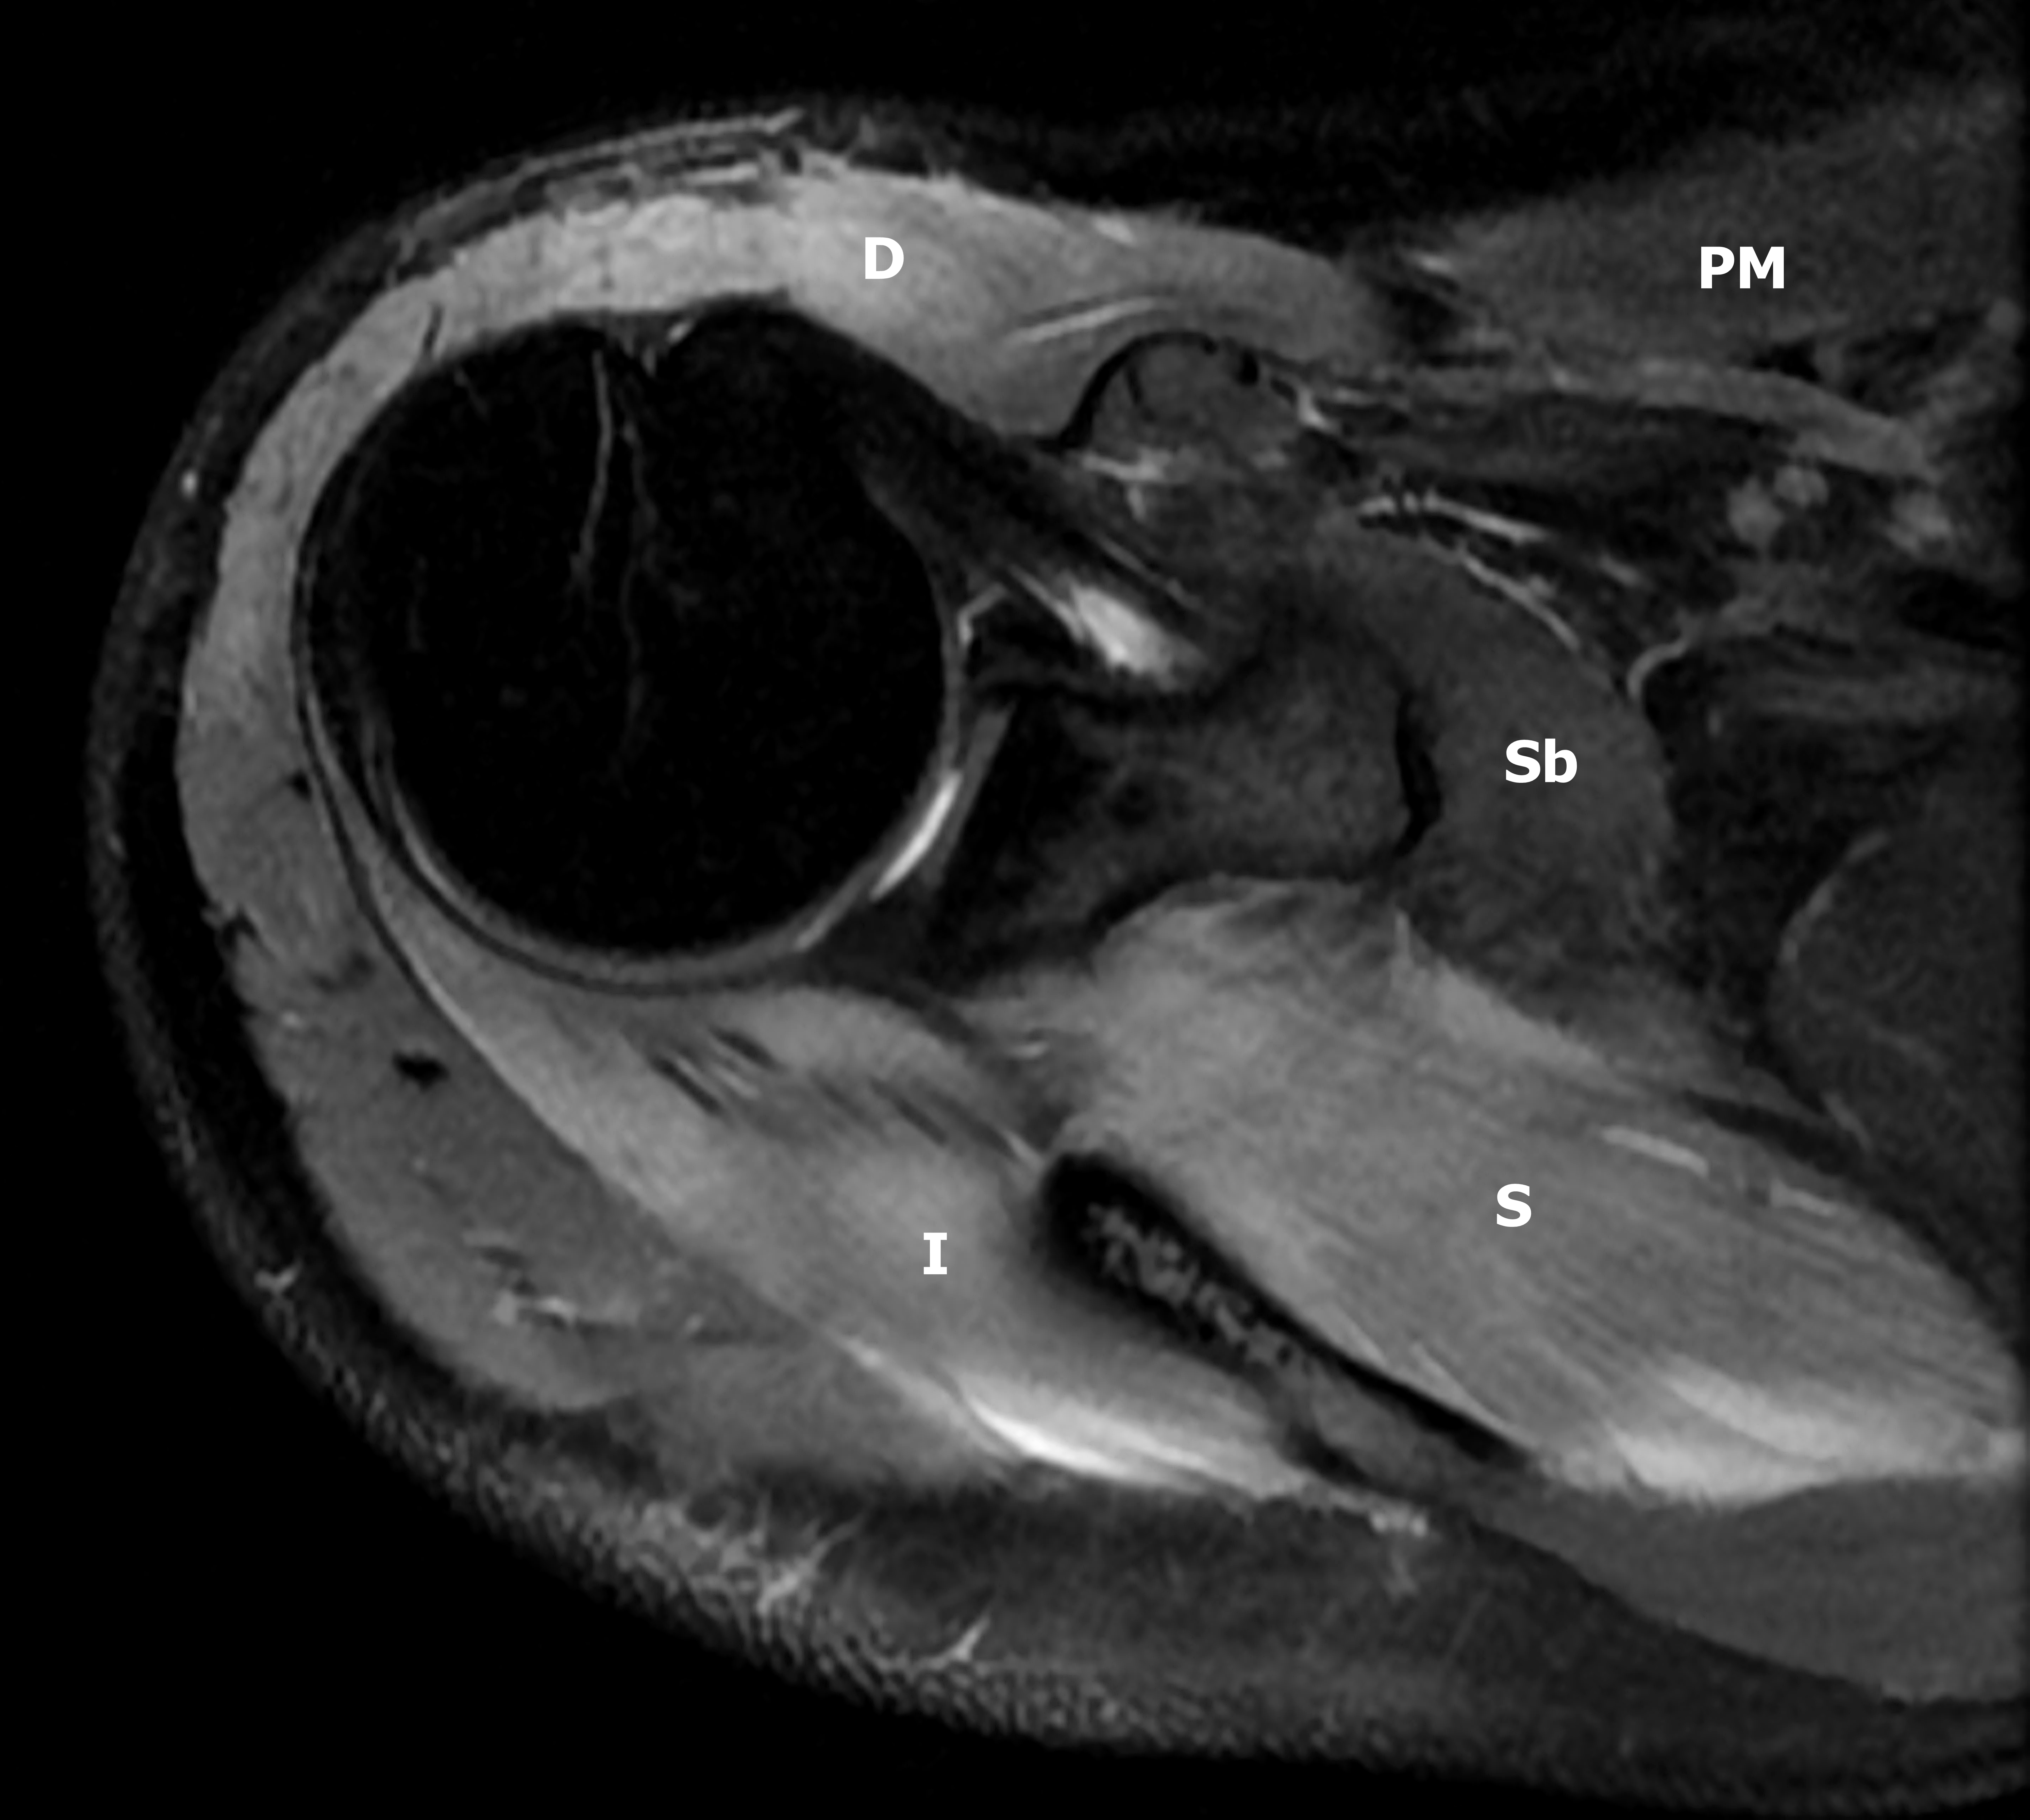

Presentación del casoMujer de 27 años de edad, con antecedentes de sepsis por estafilococo epidermidis, secundario a infección posquirúrgica de cirugía mamaria hace 3 meses, sin otros antecedentes de relevancia. Consulta en el departamento de urgencias, por presentar omalgia aguda, asociado a edema e impotencia funcional de hombro derecho, que comenzó 3 horas después de realizar actividad física intensa de CrossFit, consistente en movimientos de flexo-extensión de miembros superiores con peso.Descargas